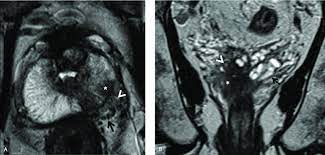

Esur Prostate Mr Guidelines 2012 Springerlink

Esur Prostate Mr Guidelines 2012 Springerlink from media.springernature.com

Pretreatment Evaluation Of Prostate Cancer Role Of Mr Imaging And 1h Mr Spectroscopy Radiographics

Pretreatment Evaluation Of Prostate Cancer Role Of Mr Imaging And 1h Mr Spectroscopy Radiographics from pubs.rsna.org